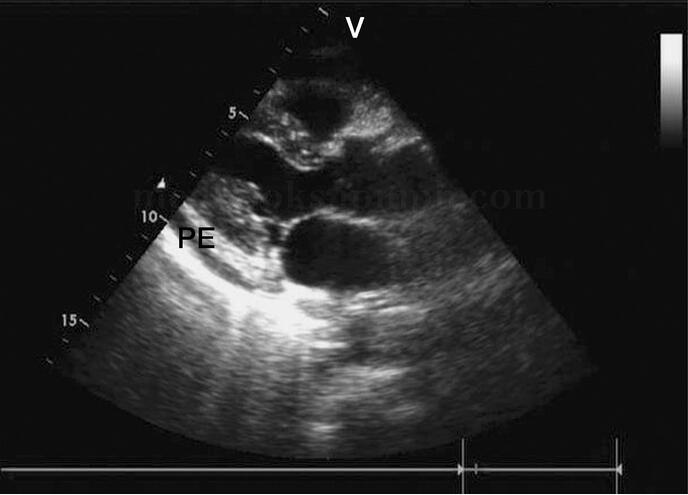

4﹒大量心包积液 心包腔内液体超过500ml,积液包绕整个心脏,此时心脏在液体内摆动,即收缩期向前、舒张期向后。

(2)二维超声心动图:整个心包腔内均可见较宽的液性暗区,液性暗区宽度大于2.0cm;心脏舒张受限,心腔内径缩小;部分患者可由于心包腔内压力

过高而使右心室前壁、右心房后壁等部位出现凹陷(图2‐1‐228)。由于心包腔内有大量液体,心脏游离在液体内,出现前后或左右摆动,即心脏摆动征。升高的右房压可使下腔静脉、肝静脉扩张(图2‐1‐229)。